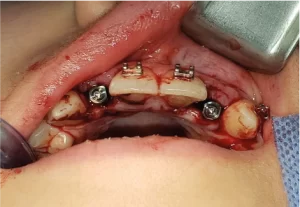

Caso de agenesia de incisivos laterales, fresado con guía quirúrgica